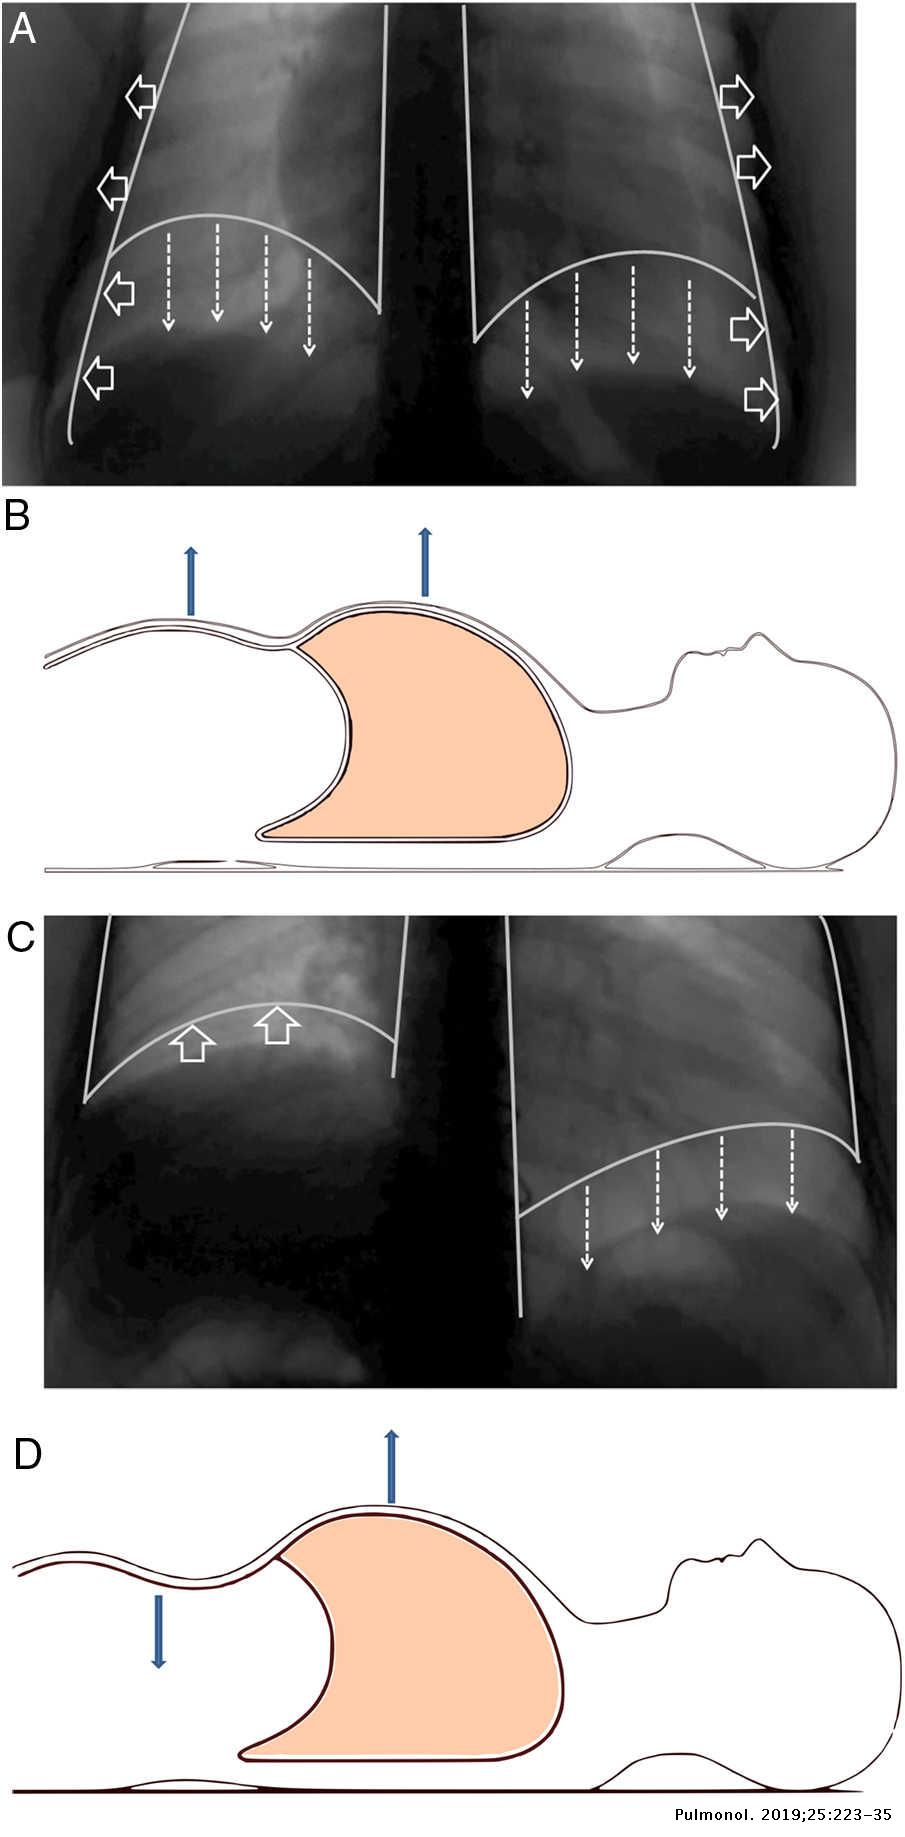

The rise in intraabdominal pressure further increases intrathoracic and lung volume by pushing the lower rib cage outward. In severe cases when there is no simple treatment that can relieve dyspnea your doctor may prescribe morphine. Diaphragmatic dysfunction caused by transverse myelitis or leukemic infiltration of the cervical spinal cord in a patient with leukemia and shortness of breath. Diaphragmatic plication a surgical procedure that pulls the diaphragm down by introducing a repeated series of continuous sutures across the diaphragm and pulling the muscle taut. A bedside fan or open window with a breeze are also simple but very effective treatments to lessen dyspnea. Depending on the severity of injury to the diaphragm some doctors recommend non-surgical options to treat the breathing issues associated with diaphragm weakness and paralysis. P E Pulmonary embolism.